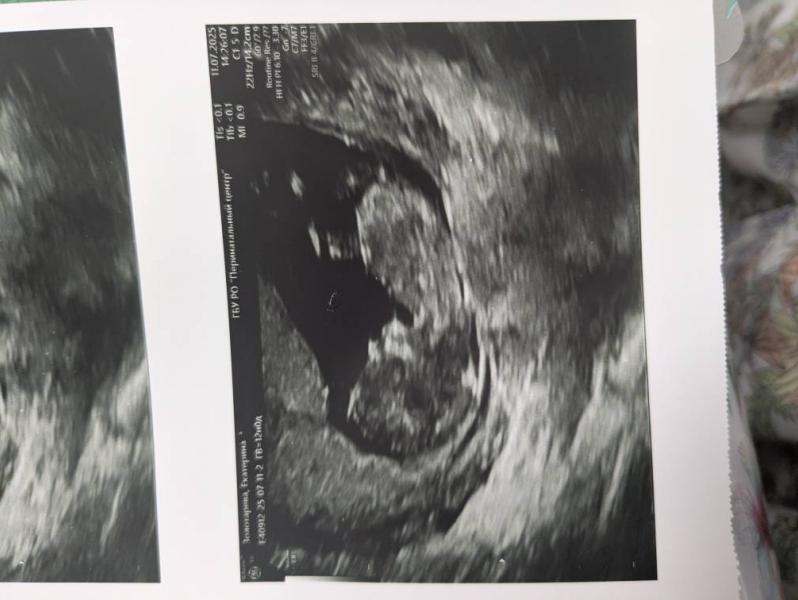

С сыном я летала всю беременность,не зная проблем. А сейчас в 7,5 недель попала на сохранение с отслойкой и гемотомой